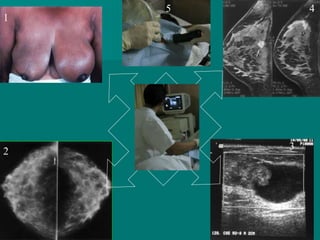

ECOGRAFIA MAMARIA

INDICACIONES DE US EN

CA DE MAMA

 Anormalidad no específica en mamografía

 Mamografía dudosa o no concluyente

 Densidad asimétrica

 Nódulo palpable o visible en mamografía

 Nódulo no palpable y poco definido en

mamografía

 Nódulo en embarazada

 Secreción por pezón

 Nódulo palpable no visible en mamografía

.- Util para diferenciar entre masas

mamarias sólidas y quísticas

.- Mujeres jóvenes menores de 35

años con tejido mamario denso.

.- Util para detectar adenopatías

axilares.

.- Si la ecografía muestra un quiste

simple (paredes finas, contenido

,libre de ecos y claro refuerzo

acústico posterior), no es necesaria

realizar ninguna otra prueba.

Servicio Ecografía INCOR

MAMOGRAFIA ECOGRAFIA

Sólido, hipoecogénico, sombra acústica

posterior. AP: Ca ductal infiltrante

Masa espiculada. AP: Ca ductal

infiltrante